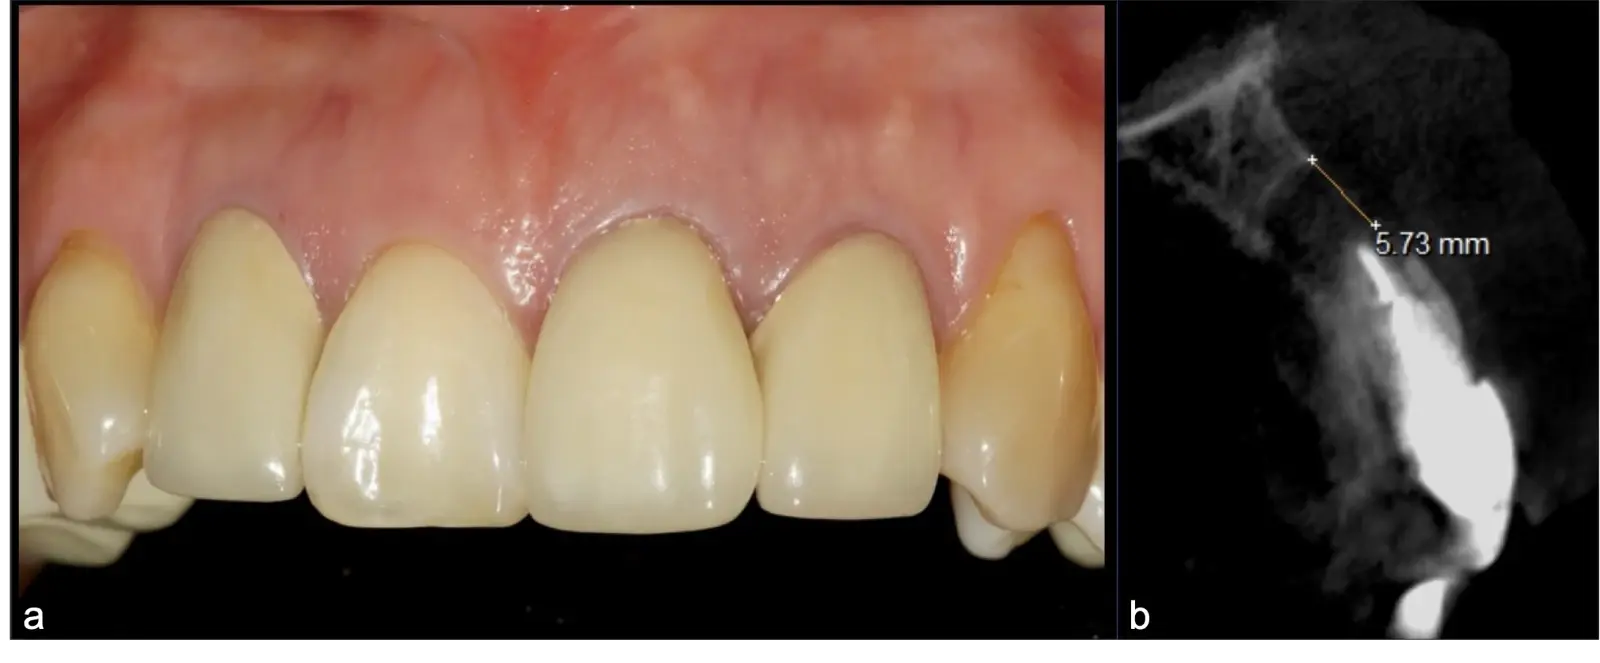

Paciente de sexo femenino de 46 años, llega a la consulta por presentar odontalgia en la pieza 2.1. Al examen clínico se observa restauración coronaria con ausencia de movilidad dentaria y la paciente refiere dolor a la percusión vertical. En la evaluación tomográfica se observó tratamiento de conducto radicular y espigo intrarradicular acompañado de imagen hipodensa a nivel apical compatible con proceso infeccioso crónico. Se procede a realizar apicectomía mediante técnica por desgaste, finalizando con la preparación y obturación de conducto radicular apical por vía retrógrada.

Figura 11. Fotografía frontal en la que el paciente presenta línea de sonrisa baja, y coronas de porcelana definitivas en incisivos superiores.

Figura 12. Fotografía frontal: restauraciones cerámicas definitivas, con ausencia de lesiones fistulosas (a). Corte sagital de TCCB pieza 2.1: imagen hipodensa compatible con lesión periapical osteolítica de aproximadamente 5.73 cm de diámetro, con compromiso de la tabla vestibular y palatina (b).